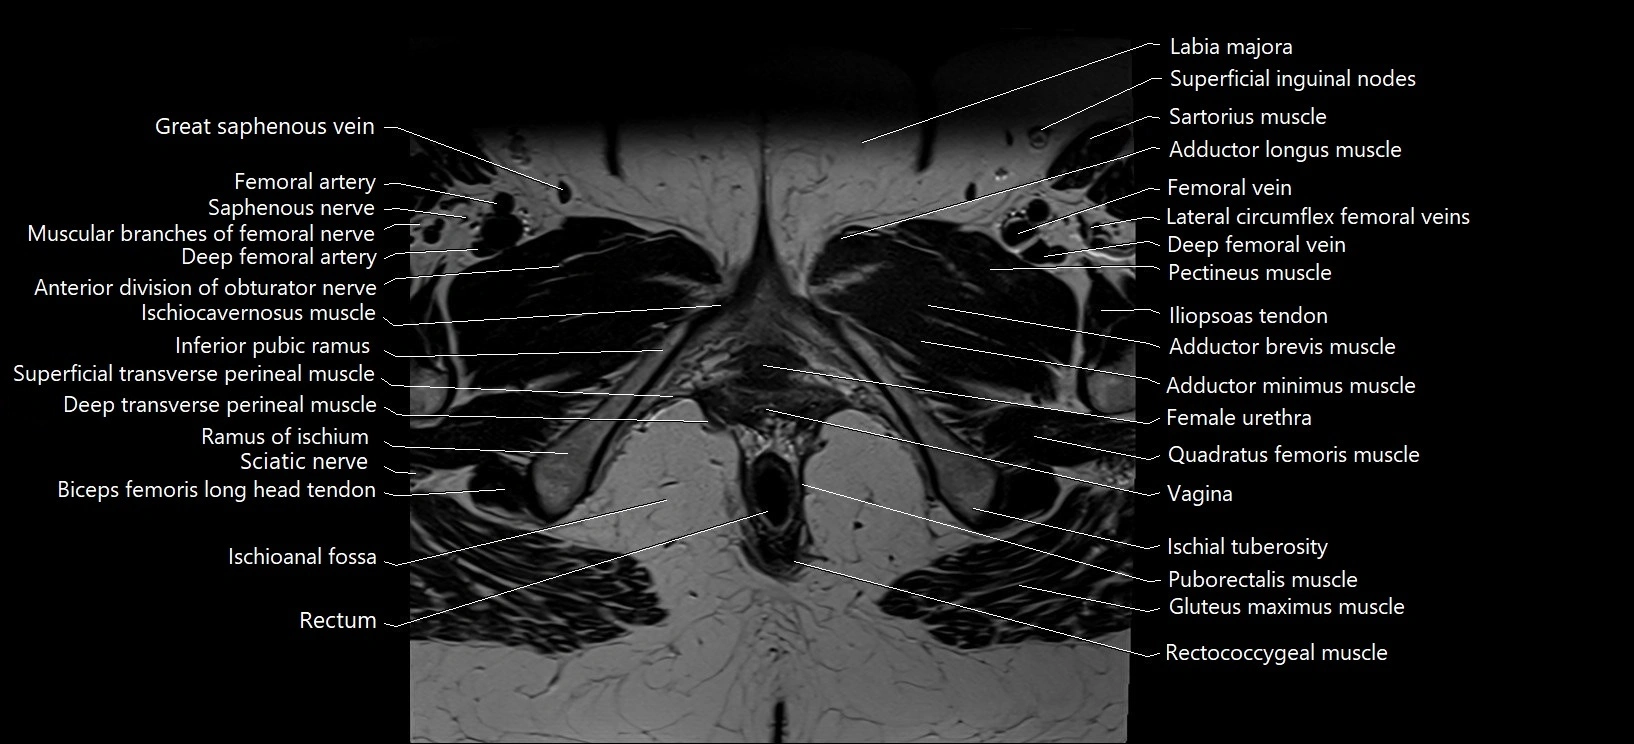

- Adductor brevis muscle

- Adductor longus muscle

- Adductor minimus muscle

- Deep femoral artery (profunda femoris)

- Deep femoral vein (profunda femoris vein)

- Deep transverse perineal muscle

- Female urethra

- Femoral artery

- Femoral nerve

- Femoral vein

- Inferior pubic ramus

- Inguinal ligament

- Ischial tuberosity

- Ischioanal fossa

- Ischiocavernosus muscle (Female)

- Labia majora

- Lateral circumflex femoral veins

- Pectineus muscle

- Puborectalis muscle

- Ramus of ischium

- Rectum

- Saphenous nerve

- Sartorius muscle

- Sciatic nerve

- Superficial inguinal lymph nodes

- Superficial transverse perineal muscle